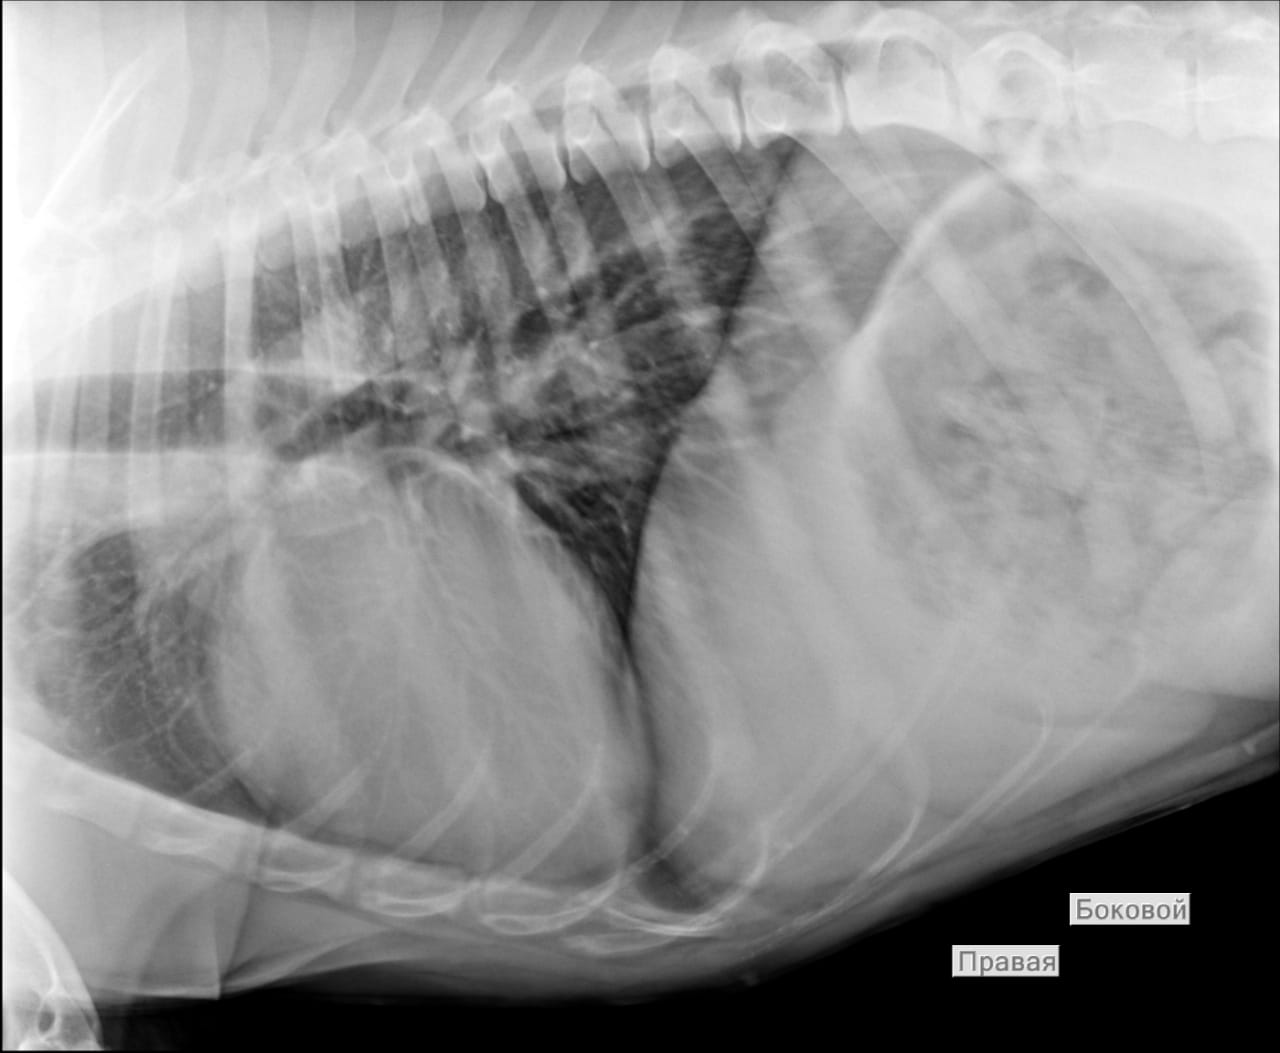

Анализы Арчи. Сердца и легких

Вложения

IMG-20220719-WA0100.jpg

IMG-20220719-WA0102.jpg

IMG-20220719-WA0104.jpg

IMG-20220719-WA0103.jpg

IMG-20220719-WA0105.jpg

Продолжение.

IMG-20220719-WA0097.jpg

IMG-20220719-WA0096.jpg

IMG-20220719-WA0099.jpg

IMG-20220719-WA0098.jpg

IMG-20220719-WA0101.jpg

Еще

IMG-20220719-WA0091.jpg

IMG-20220719-WA0092.jpg

IMG-20220719-WA0093.jpg

IMG-20220719-WA0094.jpg

IMG-20220719-WA0095.jpg

Re: Москва. Ризен Арчи из Уфы, 5 лет

Сообщение Дима »

IMG-20220719-WA0052.jpg

IMG-20220719-WA0054.jpg

IMG-20220719-WA0055.jpg

IMG-20220719-WA0090.jpg

IMG-20220719-WA0089.jpg

И чуток

IMG-20220719-WA0053.jpg

Сегодня Арчуна Ирина возила на рентген легких и сдали анализ мочи. Результат анализа мочи готов будет завтра. Рентген легких выставляю.

Ирина, ждем твоего вердикта по рентгена и можно ли нам готовить Арчи к операции по глазам.

Антибиотика курс пропили.

Лучше чем было, но явно не норма:(